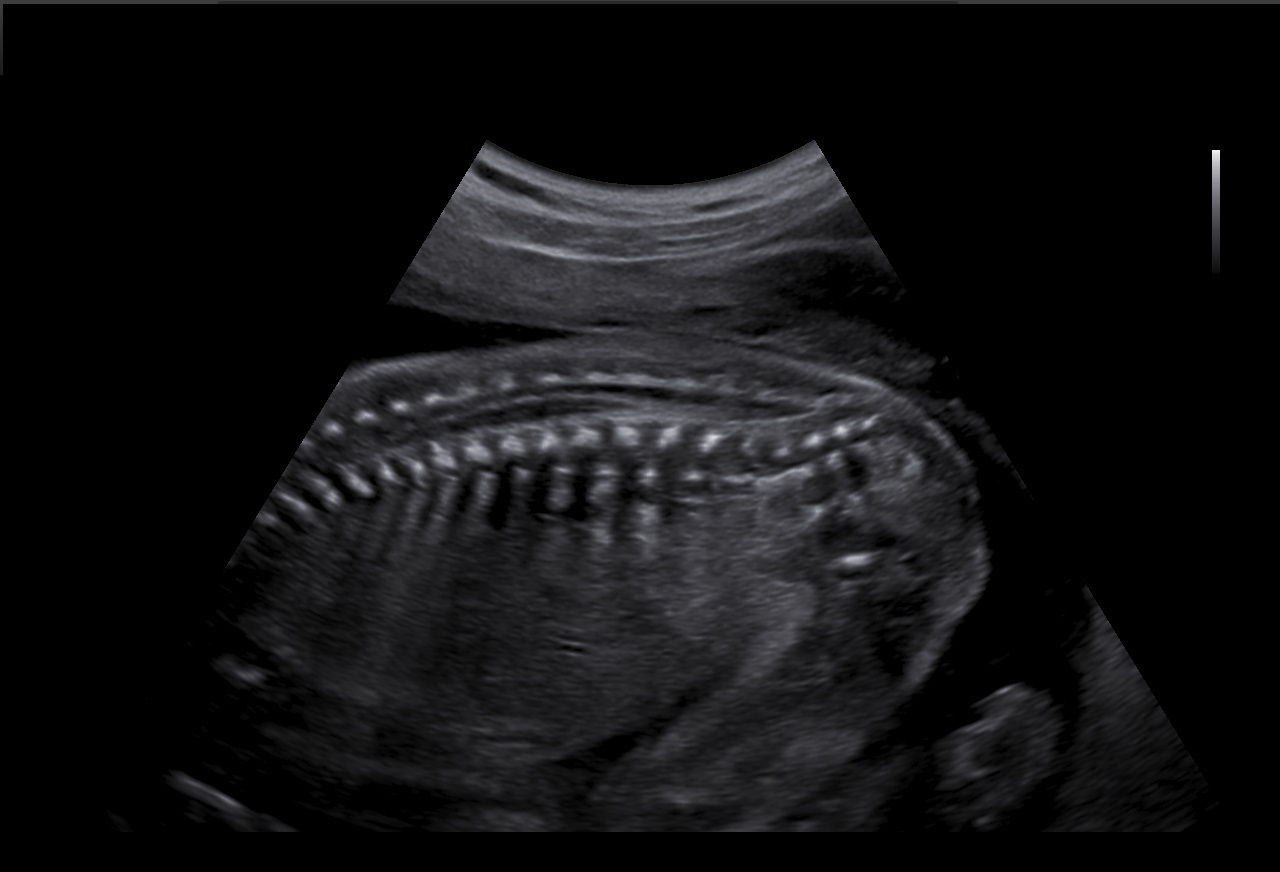

Le filtre de réduction de bruit ClearVision améliore les contours d'une structure anatomique et augmente le rapport signal sur bruit. Il permet de délivrer des images 2D plus nettes et augmente la différenciation tissulaire.